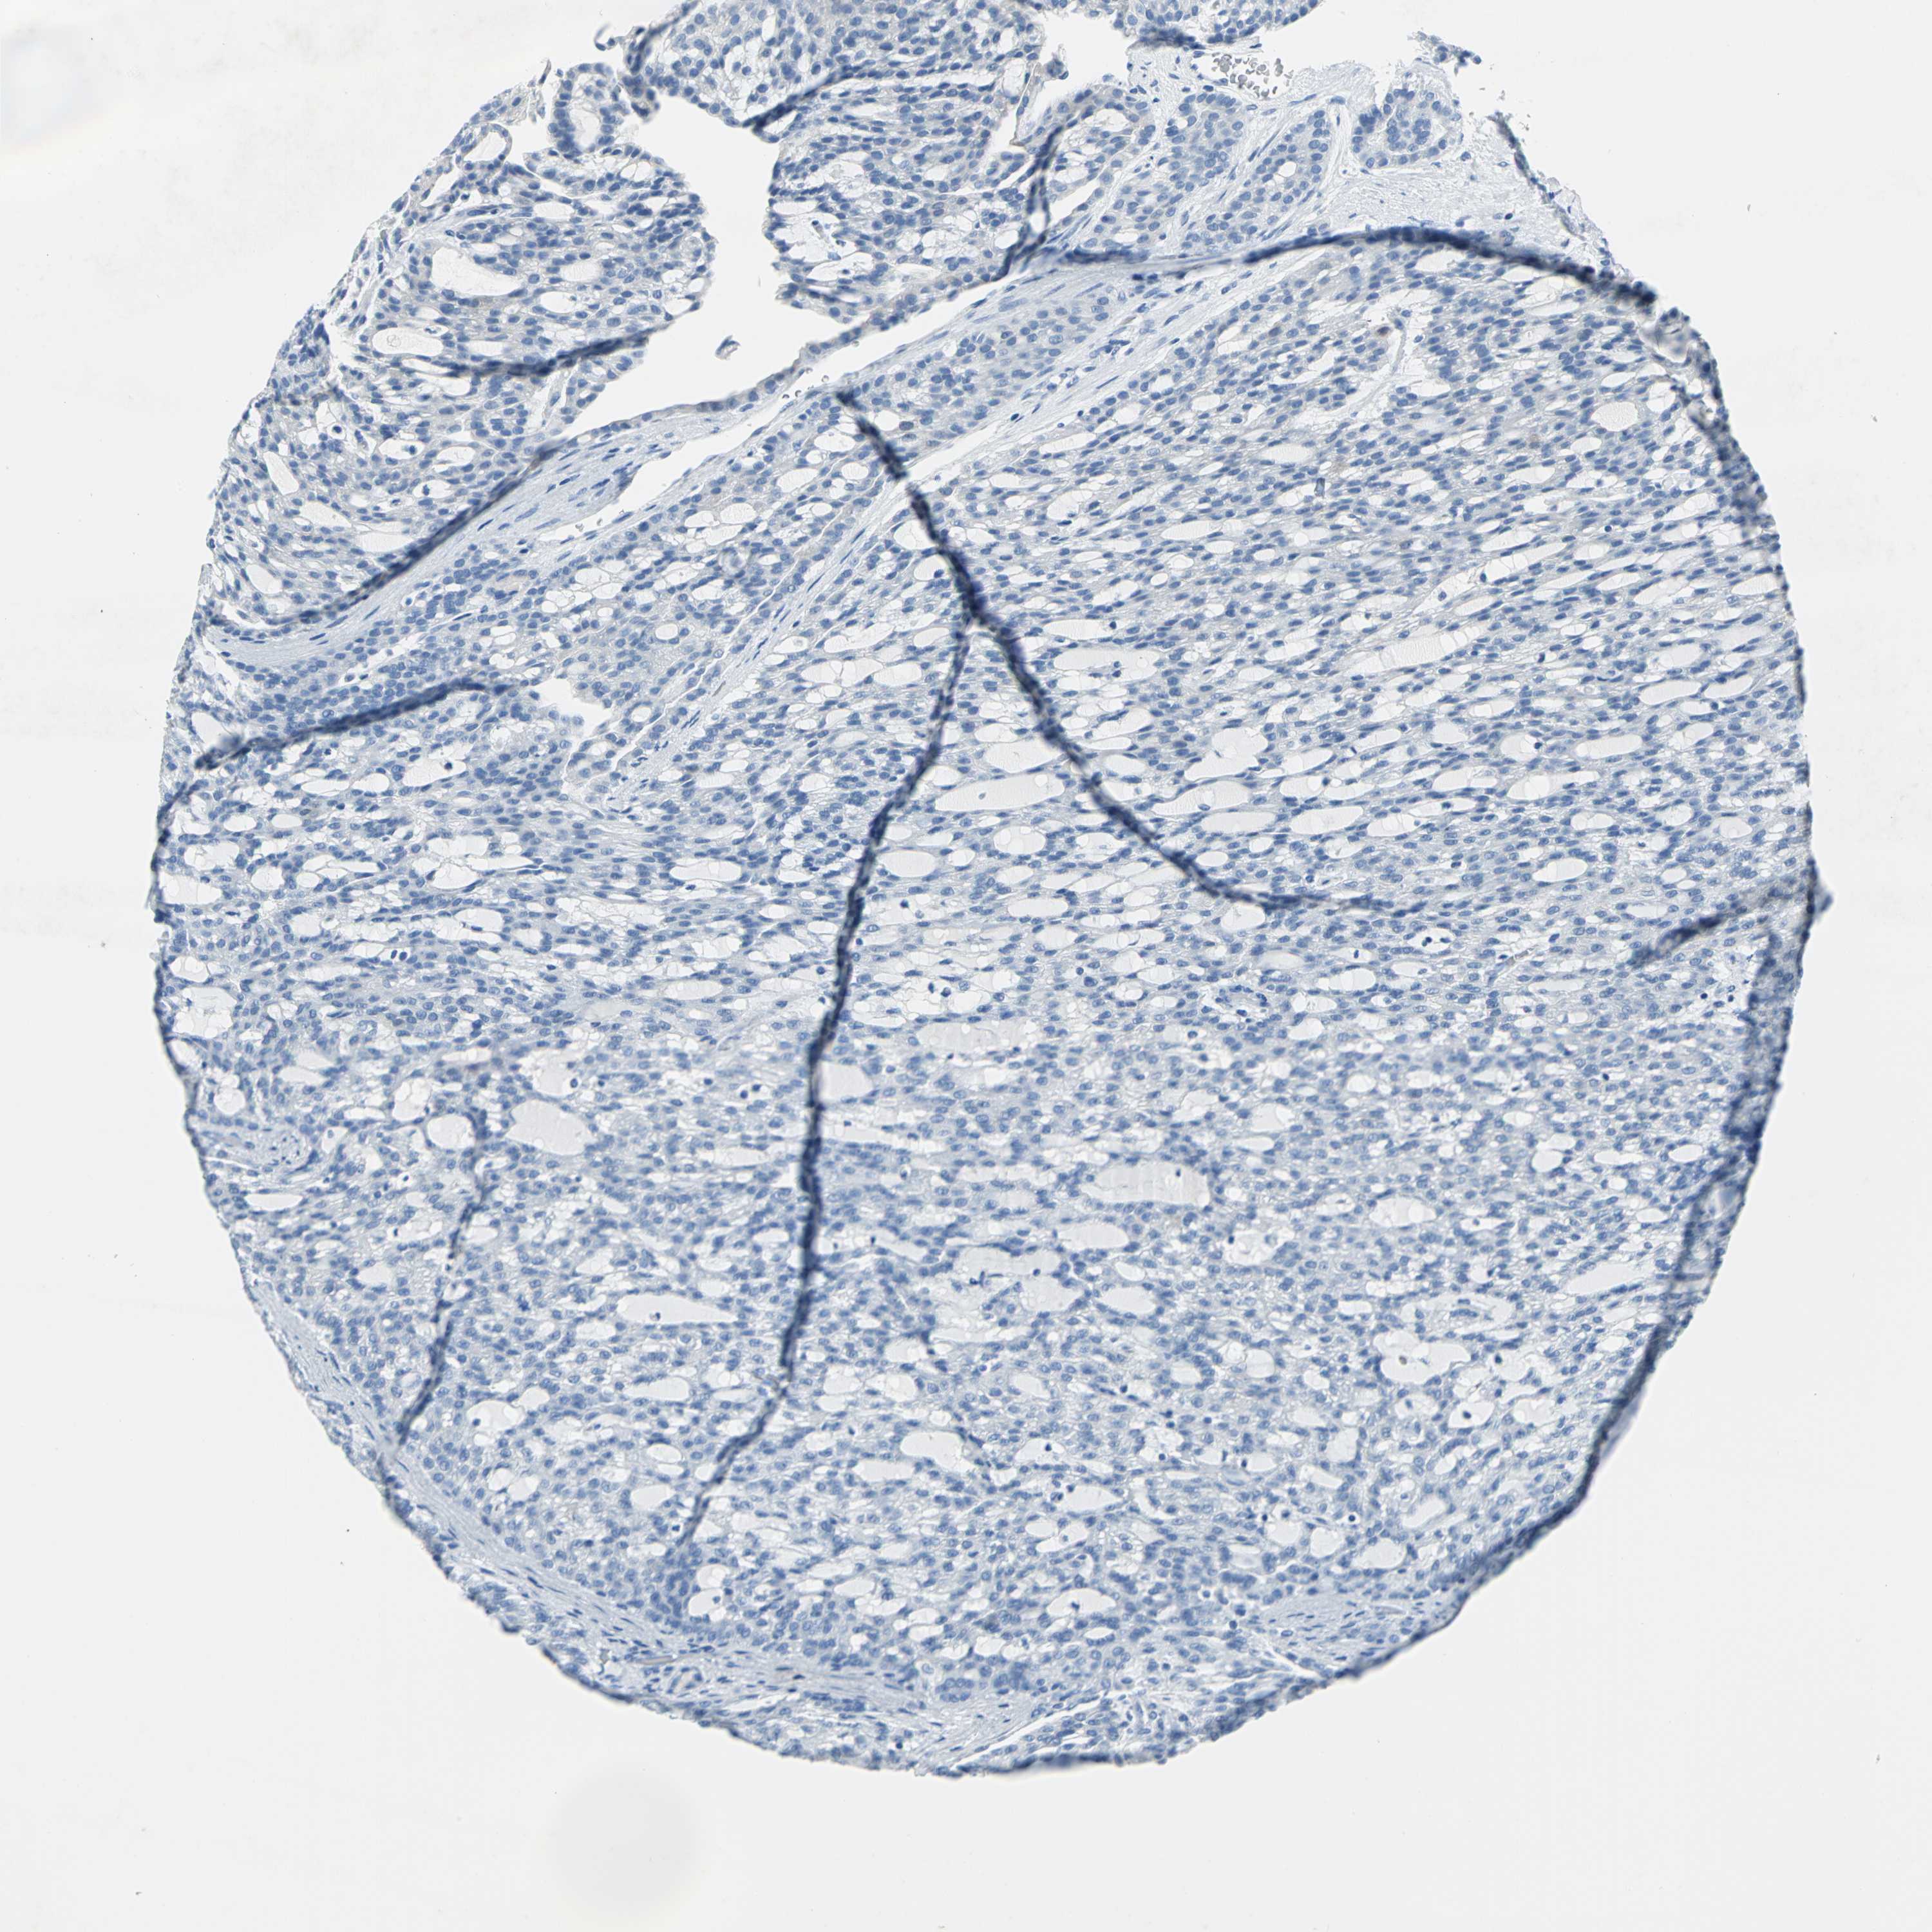

KIDNEY RENAL CLEAR CELL CARCINOMA (TCGA) - Interactive survival scatter ploti

The Survival Scatter plot shows the clinical status (i.e. dead or alive) for all individuals in the patient cohort, based on the same data that underlies the corresponding Kaplan-Meier plots. Patients that are alive at last time for follow-up are shown in blue and patients who have died during the study are shown in red.

The x-axis shows the expression levels (FPKM) of the investigated gene in the tumor tissue at the time of diagnosis. The y-axis shows the follow-up time after diagnosis (years). Both axes are complimented with kernel density curves demonstrating the data density over the axes. The top density plot shows the expression levels (FPKM) distribution among dead (red) and alive patients (blue). The right density plot shows the data density of the survived years of dead patients with high and low expression levels respectively, stratified using the cutoff indicated by the vertical dashed line through the Survival Scatter plot. This cutoff is automatically defined based on the FPKM cutoff that minimizes the p-score. The cutoff can be changed by dragging the vertical line or by entering a cutoff value in the square labeled "Current cut-off".

Under the Survival Scatter plot the p-score landscape (black curve; left axis) is shown together with dead median separation (red curve; right axis). Dead median separation is the difference in median mRNA expression between patients who have died with high and low expression, respectively. It is calculated as follows: median FPKM expression of dead patients with high expression - median FPKM expression of dead patients with low expression. This is intended to aid the user in visually exploring custom cutoffs and the associated p-scores and dead median separation.

Individual patient data is displayed and can be filtered by clicking on one or more of the category buttons on the top of the page. Categories describing expression level and patient information include: high, low, alive, dead, female, male and tumor stages. The scale of the x-axis can be toggled between linear and log-scale by clicking on the "x log" button. Mouse-over function shows TCGA ID, patient information and mRNA expression (FPKM) for each patient.

& Survival analysisi

Kaplan-Meier plots summarize results from analysis of correlation between mRNA expression level and patient survival. Patients were divided based on level of expression into one of the two groups "low" (under cut off) or "high" (over cut off). X-axis shows time for survival (years) and y-axis shows the probability of survival, where 1.0 corresponds to 100 percent.

SFN is potential prognostic, high expression is unfavorable in Kidney Renal Clear Cell Carcinoma (TCGA)